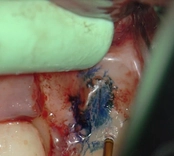

Mid-root crack repair:

Dye used to verify the crack

Crack removed

Filled with GeristoreThe patient was eating and bit down, felt and heard a “pop.” The tooth had cracked in the middle of the root. The tooth helps hold the patients partial in place and did not want to lose the tooth. The crack was removed with the laser and then restored.

The photograph is 2 months after the crack repair. The area looks like nothing was done (no redness, no scarring, etc.) and the tooth is there helping to hold the partial denture.